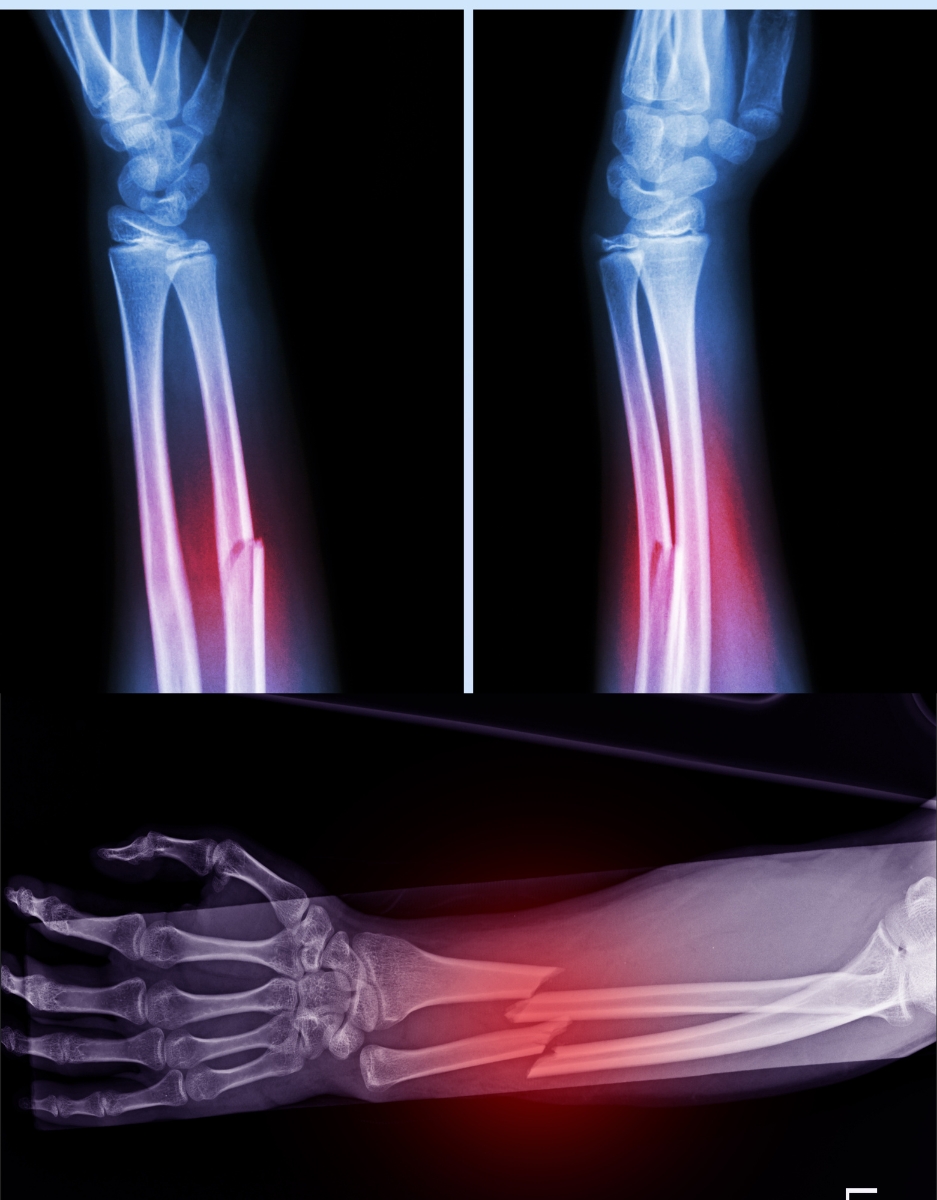

• علاج الكسور البسيطة والمعقدة باستخدام الشرائح والمسامير أو التثبيت الخارجي.

• التدخل السريع في حالات الطوارئ والحوادث لإصلاح العظام المصابة.